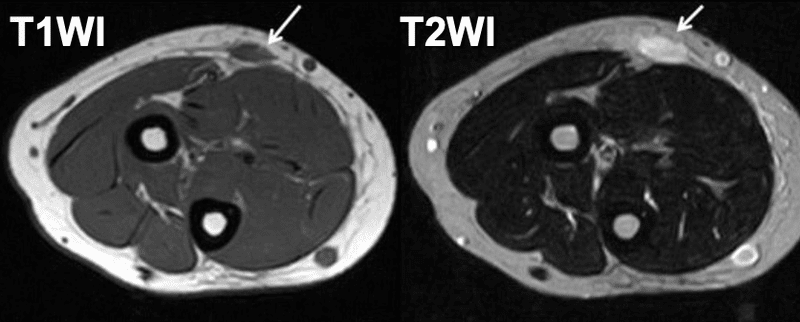

結節性筋膜炎の診断

結節性筋膜炎は一部の悪性腫瘍に似ているため、診断は困難です。それも非常にまれです。これは全腫瘍症例の 0.025% にすぎません。

結節性筋膜炎は次のようになります。

- 紡錘細胞肉腫

- 線維腫症

- 線維性組織球腫

- 良性神経鞘腫瘍

- 多形腺腫

超音波検査、MRI スキャン、または CT スキャンによる画像化は、結節性筋膜炎の特徴を特徴付けるのに役立ちます。 FNAC に続いて組織組織学的分析を行うと、確定診断を下すのに役立ちます。場合によっては、腫瘍を外科的に除去するまで診断が確定しないことがあります。